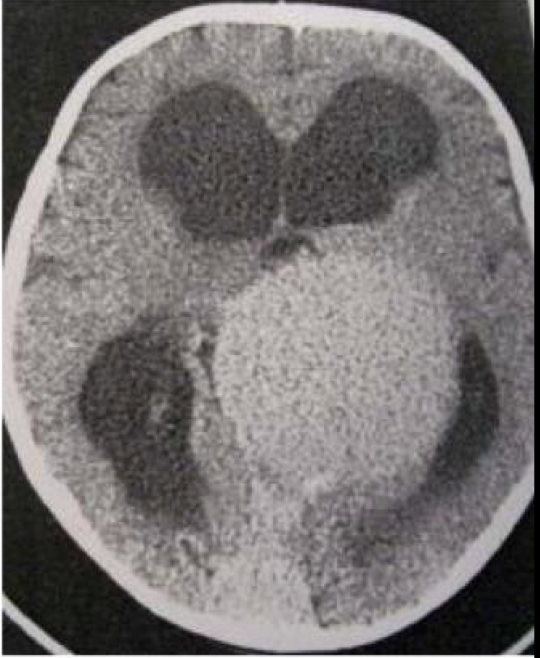

Bayi, 4 bulan dibawa dengan makrosepali. CT Scan Axial tidak enhance di bawah ini menunjukkan kelainan apa

A. Pineoblastoma

B. Malformasi Vein Gallen

C. Sinus Pericranii

D. Malformasi Kavernus

E. Teratoma

B